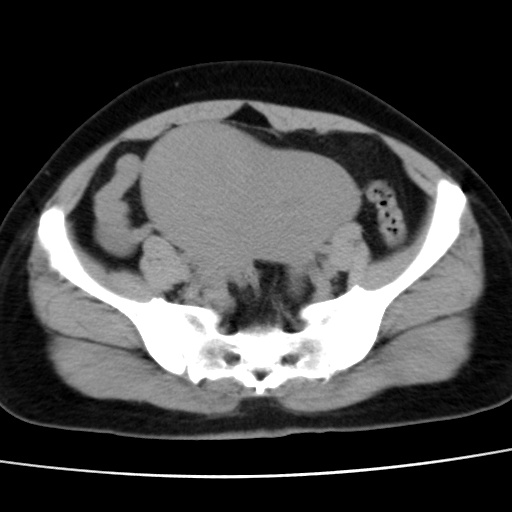

子宫多发肌瘤吗

多发性子宫肌瘤.

考虑多发子宫肌瘤,子宫直肠窝双囊性占位,另直肠周围脂肪密度增高,不知有何病史

支持考虑多发子宫肌瘤~!子宫直肠陷凹积液?

支持考虑多发子宫肌瘤~!子宫直肠陷凹积液!

子宫肌瘤,宫体部后方见液性密度影,是肠道还是子宫与直肠陷窝积液不好说,我觉得它的位置有点高

支持考虑多发子宫肌瘤!子宫直肠陷凹积液!

患者发热,而子宫直肠窝液性灶有明显边缘且局限且囊性,不除外为包裹性积液或脓肿

支持考虑多发子宫肌瘤,子宫直肠陷凹积液可能。

1)考虑子宫肌瘤可能性大。2)子宫后方囊性占位性病变,不排除卵巢囊肿可能。

考虑多发子宫肌瘤。子宫后方囊性占位性病变,不排除卵巢囊肿可能。